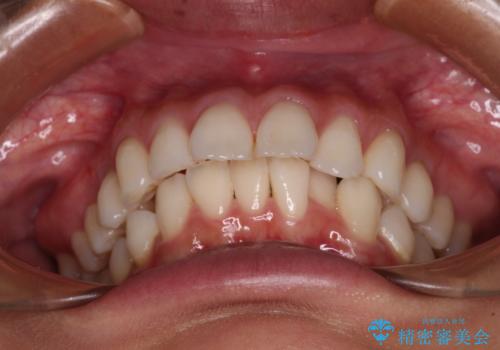

- 飛び出した前歯を気にして来院された患者様です。

口元を引っ込めるために上下左右の第一小臼歯4本を抜歯することとしました。

途中妊娠と出産がありましたが、予定よりも早く治療を終えることができました。